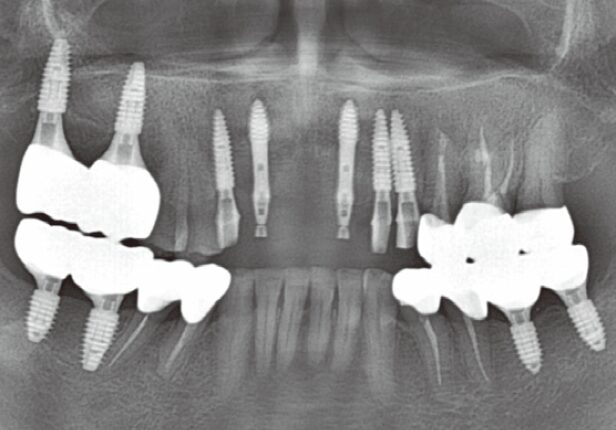

Pre-surgery panorama

Post-surgery panorama